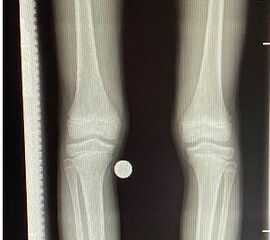

Bei offenen Wachstumsfugen kann über eine Steuerung des Wachstums mit einer Klammer (Blount-Klammer/Flex Tack) oder kleinen Plättchen (Eight Plate) eine Korrektur von Achsabweichungen in der sagittalen und coronaren Ebene erreicht werden (Abb. 8). Der Hautschnitt beträgt ca. 1,5 - 2 cm und die so versorgten Kinder können ihre Extremität direkt postoperativ schmerzadaptiert voll belasten. Die wachstumslenkende Operation mit einer Klammer oder einem Plättchen besitzt ein enormes Korrekturpotential und erspart dem Kind oder Jugendlichen umfangreiche Umstellungsosteotomien und Plattenosteosynthesen, welche eine Schnittlänge von 15 cm und eine Entlastung des operierten Beines von 4-6 Wochen erforderlich machen.

Abb. 8 a-g: Genua vara prä- und postoperativ versorgt mit Flex Tacks (a-b) und ein Genu valgum versorgt mit Eight Plate an der medialen Femurkondyle (c); Spitzfuß bei congenitalem Klumpfuß und einem Flat Top Talus mit präoperativem Röntgenbild seitlich und der deutlich nach dorsal stehender Tibia(d); intraoperative Bilder der Epiphysiodese mittels Eight Plate zur Wachstumslenkung der distalen Tibia in die Extension (e-f) und postoperativer Verlauf nach sechs Monaten mit regelrecht stehender Tibia über dem Talus durch die distale Extension (g).

Zum Lesen der Bildbeschreibung und zur Vollansicht bitte die Bilder anklicken. Bilder: A. Helmers.